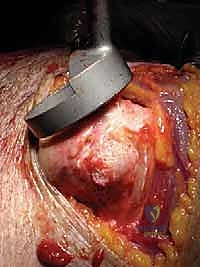

FIG 1 • A,B. Characteristic findings of cuff tear arthropathy, including superior displacement of the humeral head, “femoralization” of the proximal humerus, and “acetabularization” of the coracoacromial arch. In such a case, a conventional hemiarthroplasty, possibly using a special cuff tear arthropathy (CTA) head, may be considered.

* Anterosuperior escape: This is an exaggerated form of superior instability, occurring when the coracoacromial arch is compromised. The humeral head translates anteriorly and superiorly out of the glenoid.

FIG 1 • C,D. Anterosuperior escape of the humeral head resulting from surgical compromise of the coracoacromial arch. In such a case, a conventional arthroplasty will not provide stability, and a Delta (DePuy, Warsaw, IN) or reverse prosthesis may be considered. (Copyright Steven B. Lippitt, MD.)